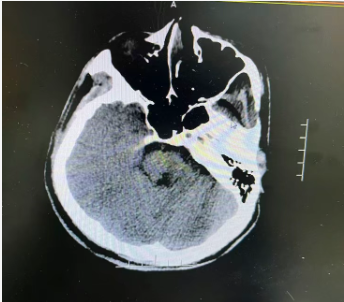

入院查体显示,患者已陷入昏迷状态,受到刺痛时无法睁眼、无法发音,肢体仅能做出屈曲反应,双侧瞳孔直径约2.5mm,对光反射存在,双侧肢体肌力约4级。紧急完善颅脑CT检查后,明确诊断为“脑干出血(脑桥)”,生命中枢遭受压迫,病情危急,随时可能进一步恶化!

孟娜副主任医师立即向科室主任侯鹏志汇报,侯主任仔细研读CT影像、分析病例,结合患者年龄、出血量及病情进展,果断判断:患者手术指征明确,决定急症行神经导航下脑内血肿清除+脑室穿刺外引流术清除颅内血肿、解除脑干压迫,才能为生命争取生机。

术前,团队快速完善CTA等辅助检查,全面排查动脉瘤等其他出血诱因,精准评估病情。术中,侯鹏志主任带领团队,依托神经导航系统这台“精准导航仪”,精准定位血肿位置,精心选取最优手术入路,全程毫米级操控,将手术切口控制在4厘米,最大限度减少对周围正常脑组织的损伤,顺利完成手术。术后患者生命体征平稳,清除血肿,神经功能逐步改善,为后续康复筑牢关键基础。